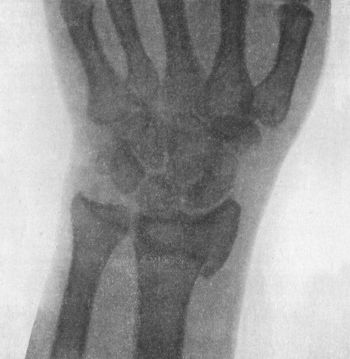

50.Dorsal Dislocation of Wrist at Radio-carpal Articulation113

51.Radiogram showing Forward Dislocation of Navicular Bone114